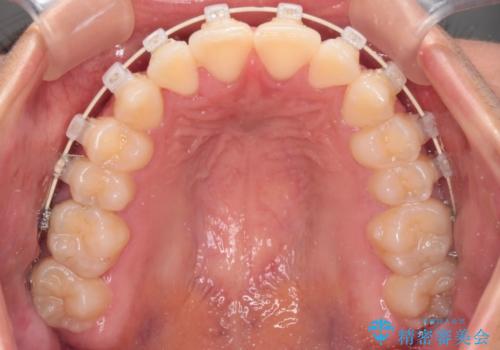

抜かない矯正 審美装置によるワイヤー治療

- 矯正装置

- 審美装置

- 前歯のガタガタを主訴に来院されました。

インビザラインも提案しましたが、装着時間を確実に確保できるか不安ということもありワイヤー矯正を希望されました。

装着時間に不安がある人は、ワイヤー矯正をおすすめしております。短期間で治療でき患者様にも満足していただきました。